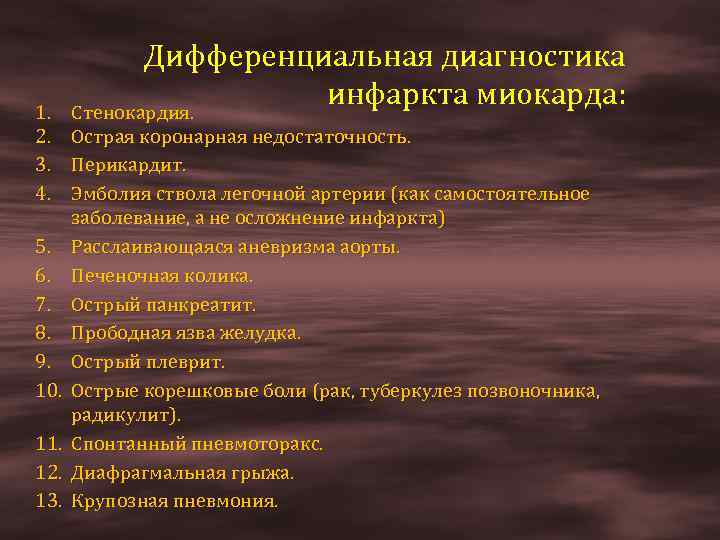

Дифференциальная диагностика заболеваний плевры